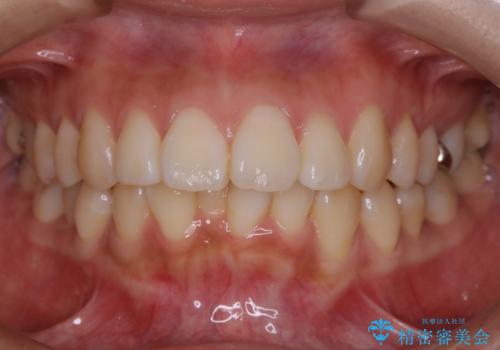

上下のデコボコを治したい インビザラインによる矯正治療